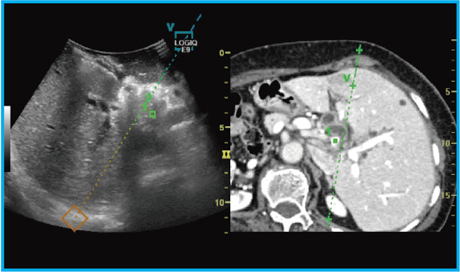

V-Navが手術で応用可能かを検証するため,preliminary studyを行った。図2 aは,術前MRIで同定された病変であるが,術前術中超音波では同定困難であった。造影超音波を施行しても同定は困難であったが,他のモダリティ画像と術中超音波を同期させることで腫瘍位置が把握可能であったことから,微小病変をとらえる有用なツールであると考える。

また,解剖学的ランドマークの確認においても,肝内のランドマークである肝前区域枝の同定の際に,needle in plane像を参照することで,肝臓の離断方向をナビゲートすることもできると考える(図2 b)。また,担癌門脈枝への染色においても,客観性を保った有用なツールであると確認できた(図2 c)。

図2 Volume Navigationの有用性の検証

a:微小病変のtargeting b:Landmarkの確認 c:担癌門脈枝への染色